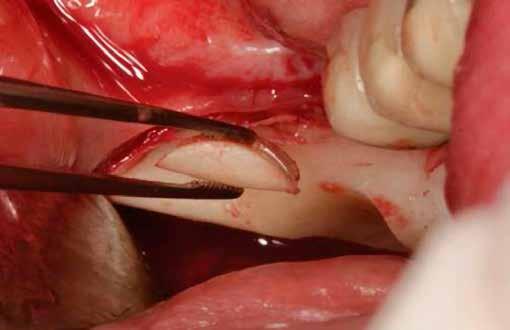

Javasolt, hogy a lehető legpontosabban ragaszkodjunk a hangár technika műtéti protokolljához. Miután a csontlemezeket oszteoszintézis csavarokkal rögzítettük, az okkluzális csontlemezt egy trepán fúróval átfúrjuk (lehetőleg az implantátum átmérőjével megegyező méretben), majd az imp-

lantátumot ezen a nyíláson keresztül helyezzük be a korábban előfúrt helyre, amelyet előtte autológ csontrészecskékkel töltünk fel.

13. ábra: Az eltávolítást követően a lemezeket a Safescraper segítségével tovább vékonyíthatjuk. – 14. ábra: A csontlemezt (domború oldalával felfelé) oszteoszintézis csavarral rögzítjük, majd a behelyezendő implantátumnak megfelelő átmérőjű trepánfúróval perforáljuk. – 15. ábra: A hézagokat autológ csontszemcsékkel töltjük ki. – 16. ábra: A csontszemcséket a defektus kontúrján belül helyezzük el. – 17. ábra: Visszahelyezzük az okkluzális csontlemezt. – 18. ábra: Gondoskodni kell az okkluzális csontlemez stabil rögzítéséről. – 19. ábra: Az implantátumot subcrestalisan helyezzük be, majd behelyezzük a zárócsavart.